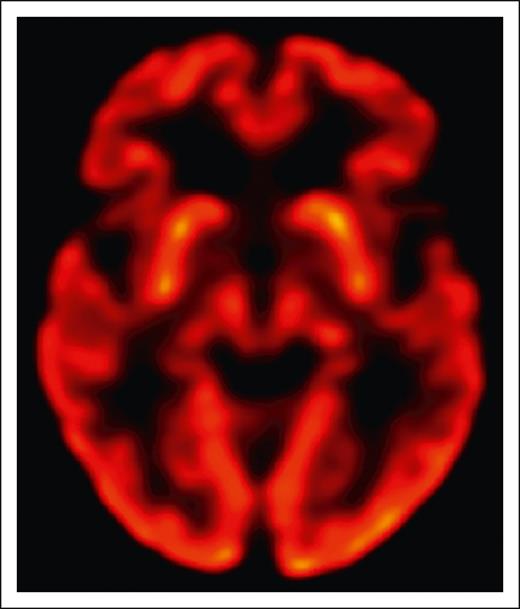

The overall gestalt of clinical examination findings in all patients reported to date is indeed most consistent with parkinsonism, a clinical syndrome that occurs with disruption of dopaminergic signaling in the brain. This can be due to loss of substantia nigra dopaminergic neurons in Parkinson disease, but also due to a variety of other mechanisms such as acquired striatal injury from stroke or hypoxia or drugs that interfere with dopaminergic neurotransmission. In the few BCMA-CAR patients where it has been reported, dopamine transporter imaging has been normal and histopathology has shown no loss of substantia nigra dopaminergic neurons. No patients with BCMA-CAR–associated parkinsonism have responded to carbidopa/levodopa. Instead, there is some evidence that the problem lies in the striatum, which receives dopaminergic innervation from the substantia nigra. Although the patient in Graham et al had normal positron emission tomography using fludeoxyglucose imaging (FDG-PET) of the basal ganglia (see figure), the ide-cel patients in Van Oekelen et al5 and in Karschnia et al had decreased uptake in the bilateral caudate nuclei. BCMA (=TNFRSF17) is detectable by RNA sequencing (RNA-seq) in the human striatum through development into young adulthood (www.brainspan.org). Since this finding comes from bulk RNA-seq data sets, it is unknown what cell type this constitutes. BCMA is not detectable by single-cell RNA-seq in other brain regions in adults (https://portal.brain-map.org/atlases-and-data/rnaseq/human-m1-10x). In adult striatum, there is no BCMA RNA detectable by in situ hybridization, and no protein is convincingly detectable by immunohistochemistry.6 Although this evidence is reassuring, we still cannot conclusively rule out low-level expression in normal adult brain.

Normal uptake in the basal ganglia on brain FDG-PET in a BCMA-CAR T-cell patient with reversible parkinsonism. See Figure 1G in the article by Graham et al that begins on page 1248.